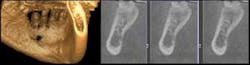

Recently, one of my patients, a 66-year-old former heavy smoker, noticed a knot under his right mandible. He had recently lost a friend to oral cancer and thus was very apprehensive. After taking digital X-rays, we also decided to take a cone beam scan with my GXCB-500â„¢ (Gendex). A view from the lingual side showed erosion through the lingual plate, right into the bone.

After consulting with an oral surgeon and using the i-CATVision software that comes with the system, a biopsy was performed. The patient was relieved to hear that the lump was not cancerous, but simply benign dysplastic tissue that would need to be monitored over time. This time, the diagnosis resulted in a lucky patient, but not from a lucky guess.